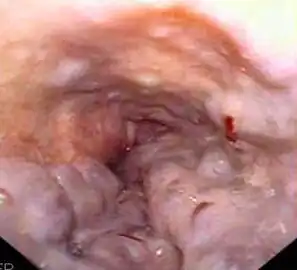

Гастроинтестинальная эндоскопия

Эндоскопические исследования выполняются с помощью специальных аппаратов-эндоскопов, вводимых пациенту через естественные отверстия — рот или задний проход и передающих изображение в исследуемом органе или на окуляр эндоскопа или на монитор. В современной практике используются два типа гибких эндоскопов: волоконно-оптические фиброэндоскопы и видеоэндоскопы, оцифровывающие видимую в объектив картинку и передающие её в таком виде на монитор или окуляр. Эзофаго-, гастро-, дуодено- и/или еюноскопия показаны при подозрении на воспаление или язву, а также другие заболевания пищевода, желудка, тонкой кишки, фатерова сосочка. Колоноскопия — эндоскопическое исследование толстой кишки, показана при наличии клинических признаков, указывающих на поражение толстой кишки, наблюдении за пациентом в процессе лечения, при осмотрах, направленных на выявление на ранней стадии онкологических и других заболеваний[22].

- Эндоскопические исследования пищевода, желудка и кишечника

-

Гибкий волоконно-оптический фиброэндоскоп -

Эндоскопия пищевода пациента с варикозным расширением вен пищевода -

Полипы фундальных желёз желудка. Изображение получено с помощью фиброгастроскопа -

Дуоденоскопия пациента с аденокарциномой двенадцатиперстной кишки